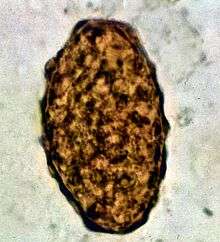

Ascaris lumbricoides is characterized by its great size. Males are 2–4 mm (0.08–0.2 in) in diameter and 15–31 cm (5.9–12 in) long. The male's posterior end is curved ventrally and has a bluntly pointed tail. Females are 3–6 mm (0.1–0.2 in) wide and 20–49 cm (7.9–19 in) long. The vulva is located in the anterior end and accounts for about one-third of its body length. Uteri may contain up to 27 million eggs at a time, with 200,000 being laid per day. Fertilized eggs are oval to round in shape and are 45–75 µm (0.0018–0.0030 in) long and 35–50 µm (0.0014–0.0020 in) wide with a thick outer shell. Unfertilized eggs measure 88–94 µm (0.0035–0.0037 in) long and 44 µm (0.0017 in) wide.[6]